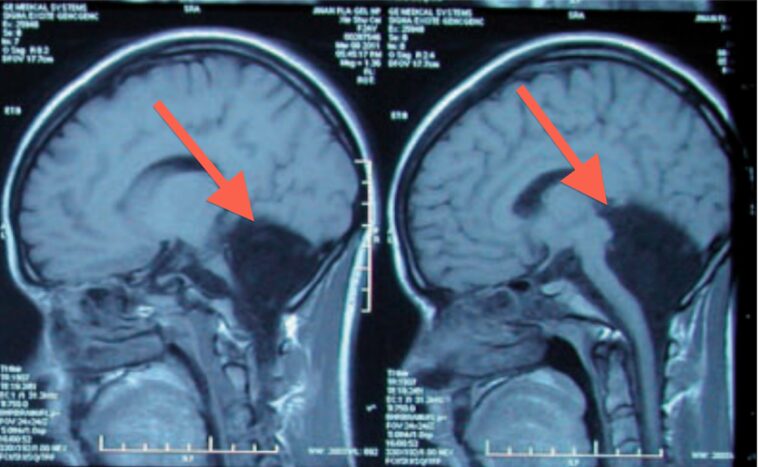

MRI scans can show enlarged ventricles caused by excess cerebrospinal fluid. They can also be used to identify causes of hydrocephalus or other conditions contributing to the symptoms.

Furthermore, Can Chiari malformation be seen on CT scan? The only real way to diagnose a Chiari I malformation, is with an MRI. A CAT Scan or CT scan may not show it, and a plain x-ray will never visualize the disorder. The MRI can show how much pressure the Chiari malformation is putting on the brainstem and the spinal cord.

Can Chiari resolve itself? An MRI study showed complete resolution of the Chiari malformation with both cerebellar tonsils being returned to their normal position within the posterior cranial fossa (Figure 2). TSE T2 sagittal MRI shows spontaneous resolution of Chiari type 1 malformation.